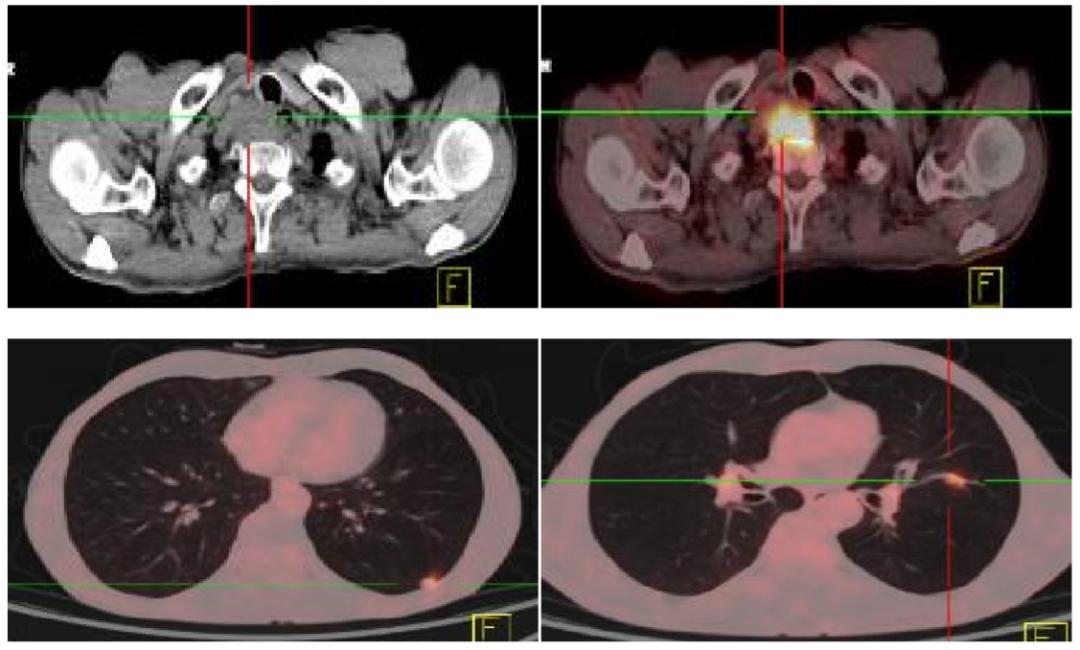

5.PET-CT(2017.09.11)

右侧颈部不规则软组织肿块代谢活跃,符合恶性病变,考虑食管来源伴周围淋巴结转移可能性大;双肺多发高密度结节代谢活跃,考虑转移。

因患者近期已行3次胃镜检查,拒绝再次胃镜检查,根据相关检查结果,初步诊断:食管上段鳞癌,颈部淋巴结转移、肺转移(cTxN+M1 IVB期)